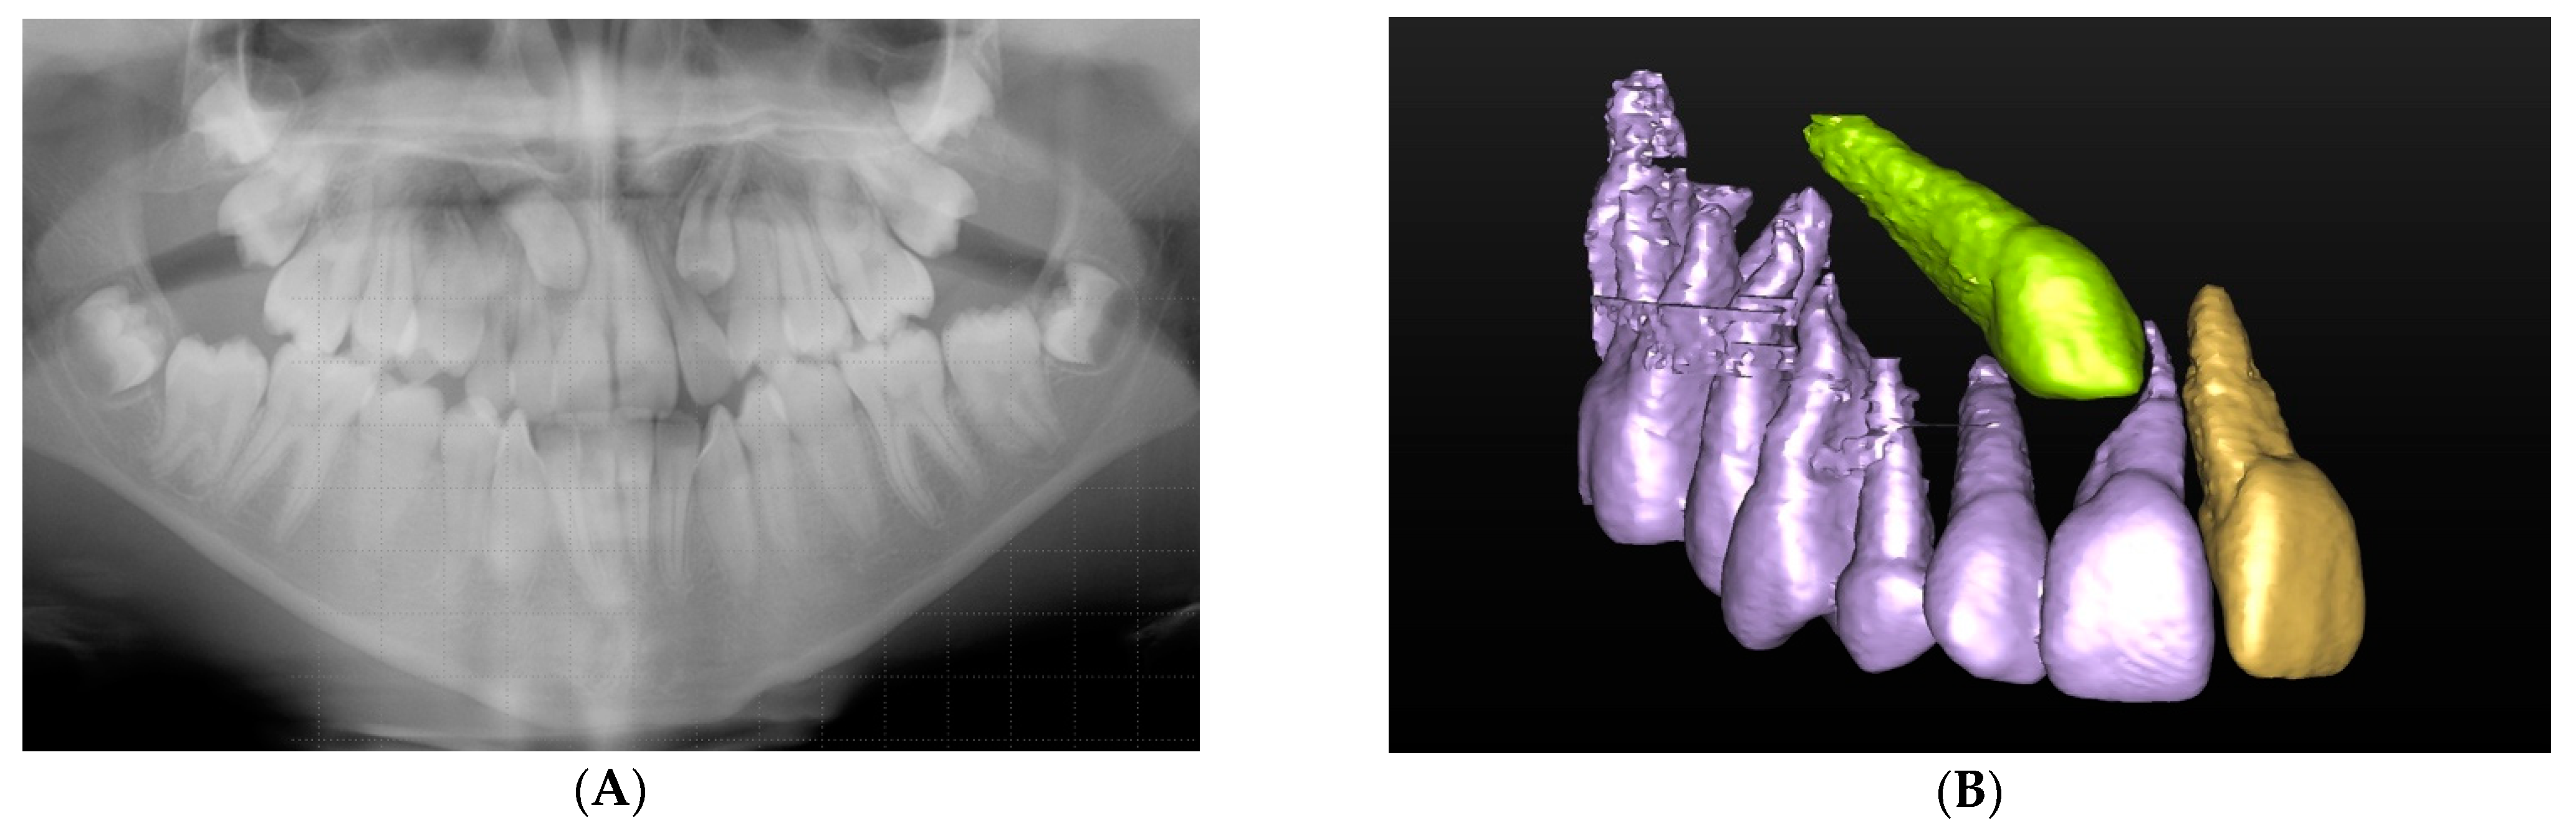

Indeed, there were multiple cases where a greater number of unerupted supernumeraries was detected following CBCT assessment and, therefore, helped avoid treatment errors. Figure 3 illustrates a case where four additional supernumerary teeth could be located on the CBCT that were not detected on the panoramic view and would have been missed. Superimposition of the anatomical structures on conventional scans could affect the management of the case as a whole and possibly result in a repeat general anaesthetic for the patient in the future.

Figure 3.

(A) Panoramic radiograph demonstrating multiple supernumerary teeth in the maxilla and mandible. There are three clearly visible supernumerary teeth in the maxilla (marked with asterisks. (B) Three-dimensional (3D) segmented reconstruction of the right maxilla viewed from the palatal aspect showing two further maxillary supernumerary teeth marked with an asterisk, one palatal to the upper right central incisor and the other palatal to the upper right canine (©DentsplySirona-Simplant® Pro).